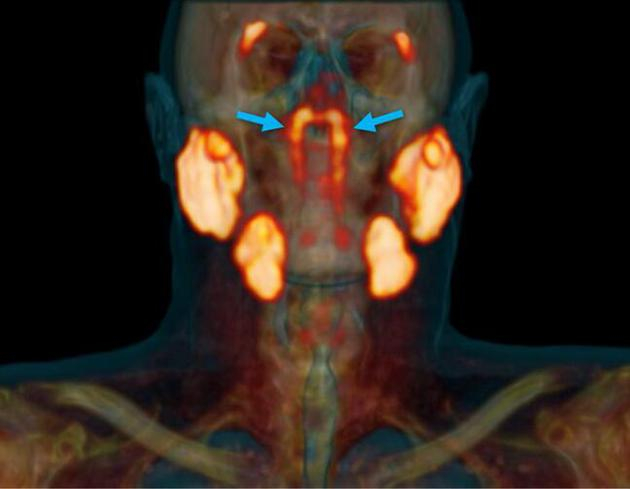

在仔细读取一组扫描图时,研究人员注意到头部有两个很不寻常的结构。这是两个扁平、细长的腺体,长约4厘米,不显眼地挂在连接耳朵和喉咙的管状结构上。研究人员对这些图像感到十分困惑。他们首先查看了100份历史上的扫描图像,还对两具尸体进行组织解剖,发现这些腺体与位于舌头下方的已知唾液腺有相似之处。这些新腺体还连接着较大的引流管,可能暗示着它们正在将液体从一个地方输送到另一个地方。

根据这组腺体所处的位置,研究人员将其命名为“咽鼓管腺”(tubarial glands),因为腺体十分靠近咽鼓管圆枕(torus tubarius)

我们尚不完全清楚这些腺体是如何逃脱解剖学家的“法眼”。不过,研究作者之一、荷兰癌症研究所的放射肿瘤学家沃特·沃格尔说:“这个位置并不容易进入,你需要非常灵敏的成像技术才能检测到它。”人体其他较大的唾液腺通常靠近皮肤表面,可以很容易通过解剖发现,但新的这组唾液腺隐藏在头骨底部,就不那么容易找到了。根据这组腺体所处的位置,研究人员将其命名为“咽鼓管腺”(tubarial glands),因为腺体十分靠近咽鼓管圆枕(torus tubarius)。

在这项研究中使用的扫描成像技术被称为PSMA PET/CT(正电子发射体层摄影术/计算机体层摄影术),也被专门用于确定这些患者中肿瘤的生长。研究人员称,只有更新的PSMA-PET/CT成像技术才能检测到这些唾液腺的结构,这超出了超声波、CT和核磁共振(MRI)扫描等技术的可视化能力。